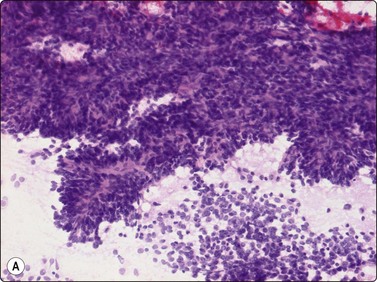

Smears from synovial sarcoma are usually highly cellular (Fig. 15.57A). The typical appearance is a mixture of tissue fragments and dispersed cells. Mitotic figures can be found in almost every case, especially in the tissue fragments. Bare nuclei are common. A hemangiopericytoma-like vascular pattern with branching capillaries (’staghorn’ pattern) is commonly seen in fragments. The cells are small to medium in size. Nuclei are rounded or ovoid with finely granular, bland chromatin and nucleoli are small and inconspicuous. Intact cells have thin uni- or bipolar cytoplasm. Vaguely acinar-like structures may be seen in the periphery of fragments (Fig. 15.57B). Mast cells are prominent in some cases. A myxoid background matrix has been reported in some cases.74 An obvious biphasic pattern is only infrequently seen in our experience. The cytology of mono- and biphasic synovial sarcoma has been reported in two large series.75,76 The cytomorphology of the poorly differentiated variant77 (involving the entire tumor or focally in other subtypes) is relatively unknown and has been described in few cases (Fig. 15.58).78-80 Poorly differentiated fibrosarcoma-like synovial sarcoma is extremely difficult to distinguish from MPNST and the rare fibrosarcoma. A reliable cytologic diagnosis of synovial sarcoma is important since neoadjuvant therapy is commonly applied before surgery. Even if synovial sarcoma is strongly suspected in an FNB smear, adjunctive diagnostic methods are almost always necessary to reach a confident diagnosis. The majority of synovial sarcomas stain positively for EMA and keratins 7 and 19 (although often focally); positive staining for CD99 and bcl-2 has also been reported. Cytogenetic analysis is a most important valuable adjunct. FISH (Fig. 15.59) and RT-PCR of aspirated material used for detection of the two most common gene fusion products (SYT/SSX1 and SYT/SSX2, respectively) is more effective than chromosomal analysis of cytologic material to diagnose the translocation t(X;18)(p11;q12).81

image image

Fig. 15.57 Synovial sarcoma

(A) Smears are usually highly cellular; the typical appearance is a mixture of tissue fragments and dispersed cells (H&E, LP); (B) Vaguely acinar-like structures may be seen in the periphery of fragments (MGG, HP).